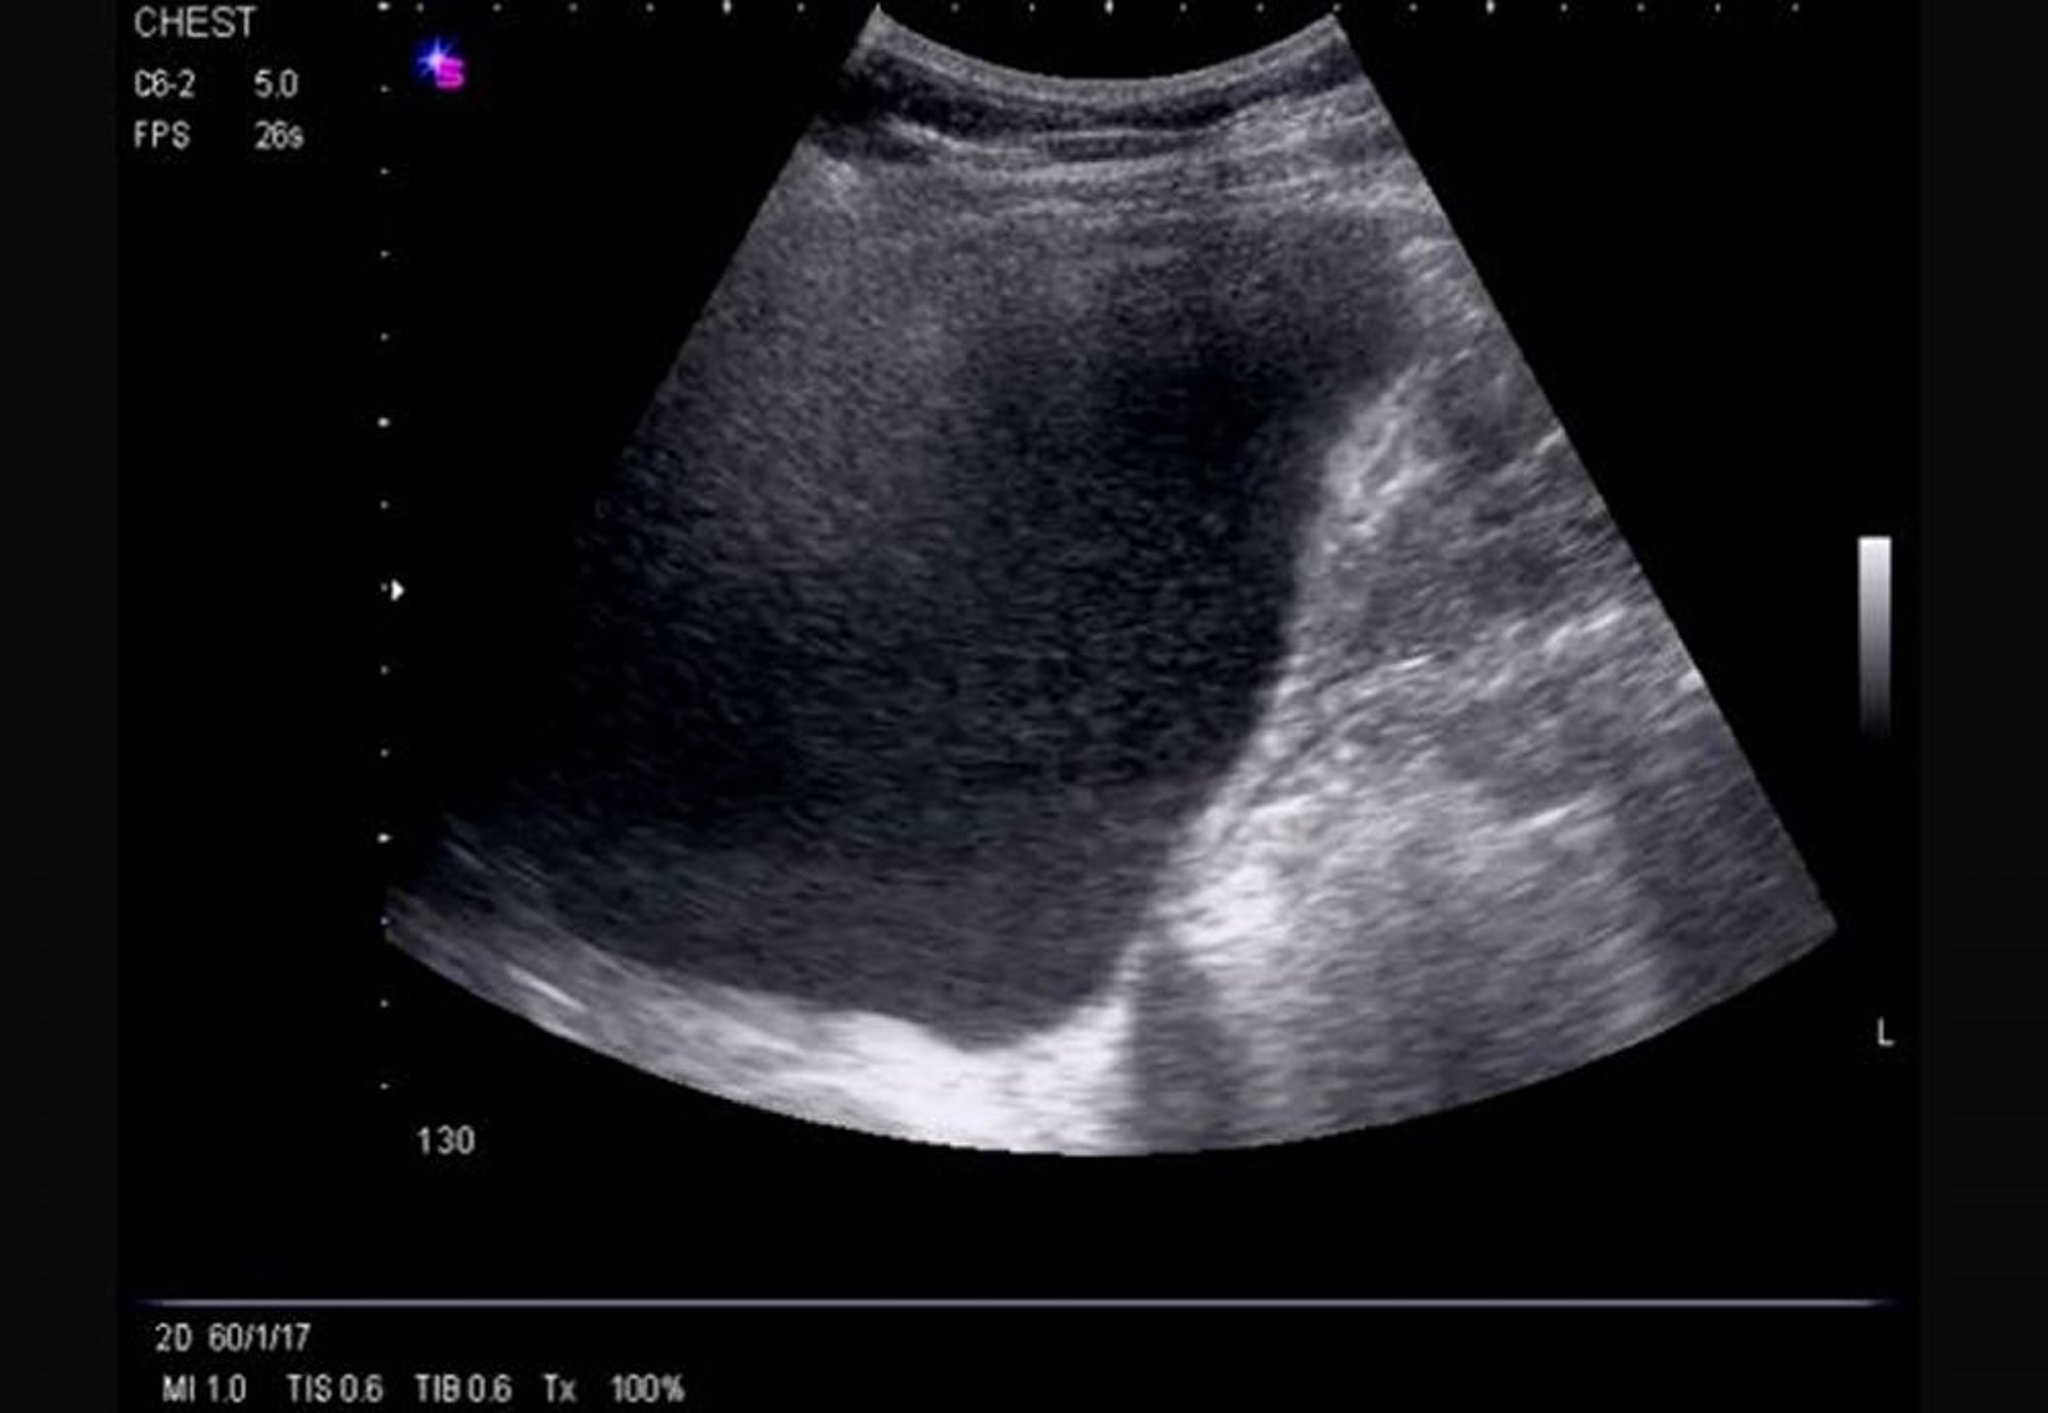

Échographie thoracique de profil (droite)

Cette échographie montre un épanchement massif, droit, à écoulement libre provoquant l'inversion de l'hémidiaphragme et démontrant une échogénicité.

Image courtoisie de Najib M. Rahman, BMBCh MA (oxon) DPhil.